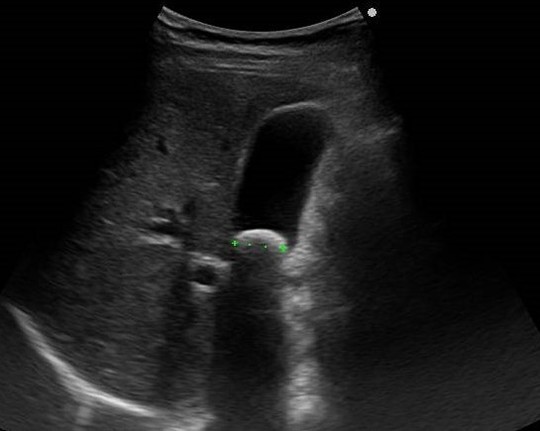

・数週前より胃のあたりの痛みがあり来院されました。

・悪い病気があるのではないかという不安と、検査そのものについての不安があり、来院後症状をうかがい、超音波検査を行いました。胆のう結石や膵臓の腫瘍などの疾患が無いことを超音波検査で確認しました。

・超音波検査だけでは確認ができない食道や胃、十二指腸の病変については内視鏡検査を行うこととしました。内視鏡検査(胃カメラ)がつらいのではないかという不安があるため、鎮静剤によるつらくない内視鏡検査について説明しました。安心して検査を受けていただきました。